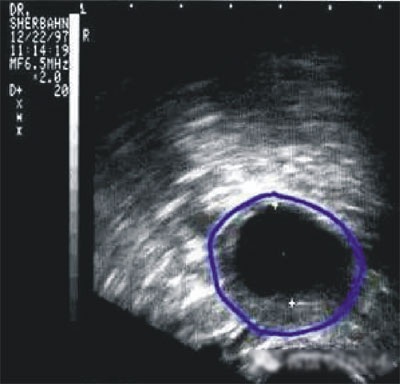

第三步:排卵監(jiān)測

常用的監(jiān)測排卵方法有基礎體溫測定(BBT)、陰道B超監(jiān)測排卵、血清性激素測定等。

(圖:排卵監(jiān)測)

陰道B型超聲動態(tài)監(jiān)測卵泡的發(fā)育及排卵,是監(jiān)測排卵最準確可靠的方法。通過陰道B超檢查可以了解子宮及雙側(cè)附件(卵巢和輸卵管)區(qū)的基本情況,測定卵巢內(nèi)的竇卵泡計數(shù),評估卵巢儲備功能,動態(tài)監(jiān)測排卵。